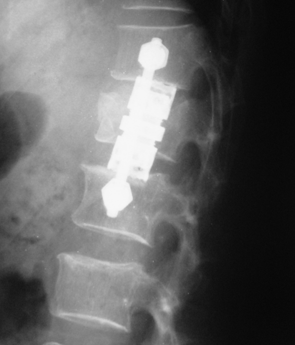

Traumatic fracture with Burst fracture D12 with Cauda equina syndrome. Operated retroperitoneal anterior surgery.